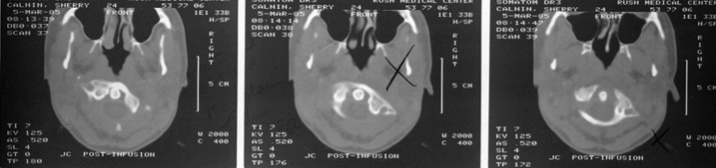

23

This x-ray was difficult to obtain due to severe acute torticollis.

What is the diagnosis?

A

Atlantoaxial rotary fixation

note asymmetry of paraodontoid spaces

24

How will this patient present?

Acute torticollis

etiology can be post-traumatic or post-infectious